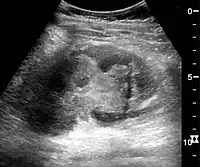

Masses are seen as a distortion of the normal renal architecture. Most renal masses are simple cortical renal cysts with a round appearance and a smooth thin capsule encompassing anechoic fluid. The incidence increases with age, as at least 50% of people above the age of 50 have a simple cyst in one of the kidneys. Cysts cause posterior enhancement as a consequence of reduced attenuation of the ultrasound within the cyst fluid (Figure 5). The simple cyst is a benign lesion, which does not require further evaluation.[1]

Complex cysts can have membranes dividing the fluid-filled center with internal echoes, calcifications or irregular thickened walls. The complex cyst can be further evaluated with Doppler US, and for Bosniak classification and follow-up of complex cysts, either contrast-enhanced ultrasound (CEUS) or contrast CT is used (Figure 6). The Bosniak classification is divided into four groups going from I, corresponding to a simple cyst, to IV, corresponding to a cyst with solid parts and an 85–100% risk of malignancy.[1] In polycystic kidney disease, multiple cysts of varying size in close contact with each other are seen filling virtually the entire renal region. In advanced stages of this disease, the kidneys are enlarged with a lack of corticomedullary differentiation (Figure 7).[1]